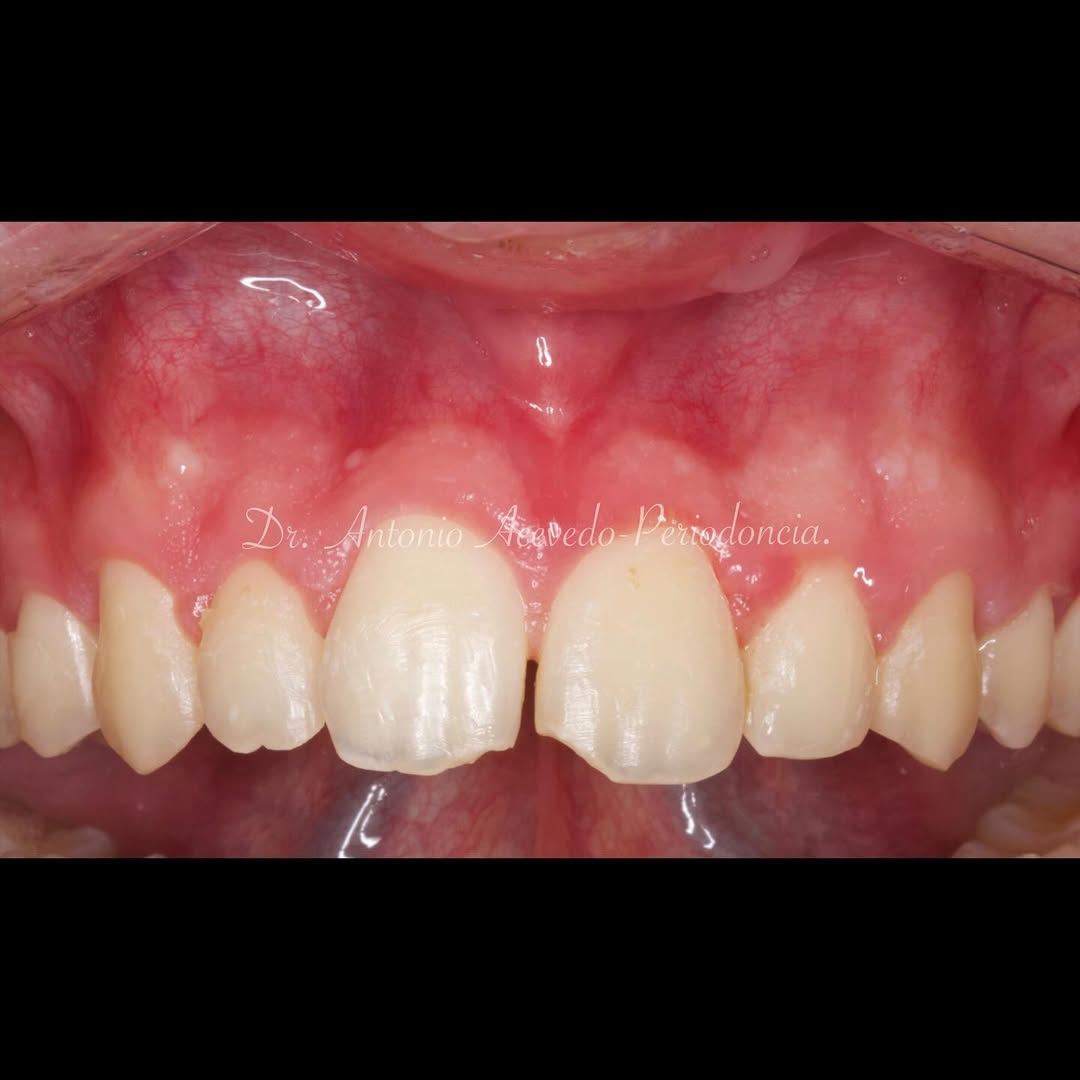

Los problemas estéticos de una sonrisa no se ciñen sólo a los dientes eso lo sabemos todos. Por eso un curso de Perio-Estética, es fundamental para poder abordar casos de Estética y solo a través de un correcto diagnóstico previo podremos realizar un adecuado plan de tratamiento, muchas